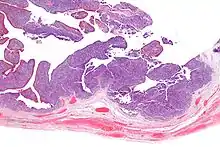

| Micrograph of transitional cell carcinoma of the ovary. H&E stain. |

TCC of the ovary is diagnosed by examination of the tissue by a pathologist. It has a characteristic appearance under the microscope and distinctive pattern of immunostaining.[2]

Low mag.

Low mag. Very high mag.